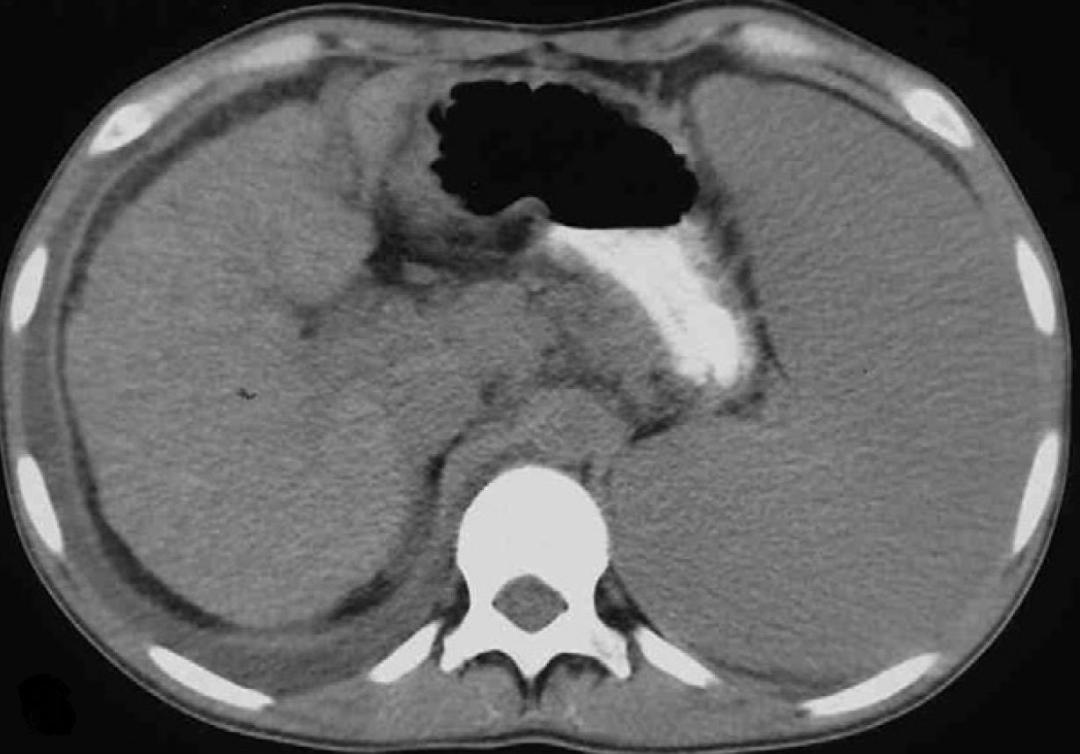

但患者真的是“肝硬化”吗?患者又做了磁共振检查(MRI):

患者做了肝脏病理,肝组织铁染色(++)。

最后真相大白,该患者为继发性含铁血黄素沉着症。过多的含铁血黄色在肝脏沉积,导致肝脏继发的表面不光整,造成“肝硬化”的假象。我们再仔细看肝脏CT图像,肝脏密度升高,明显高于同层面脾脏、腹主动脉管腔密度。